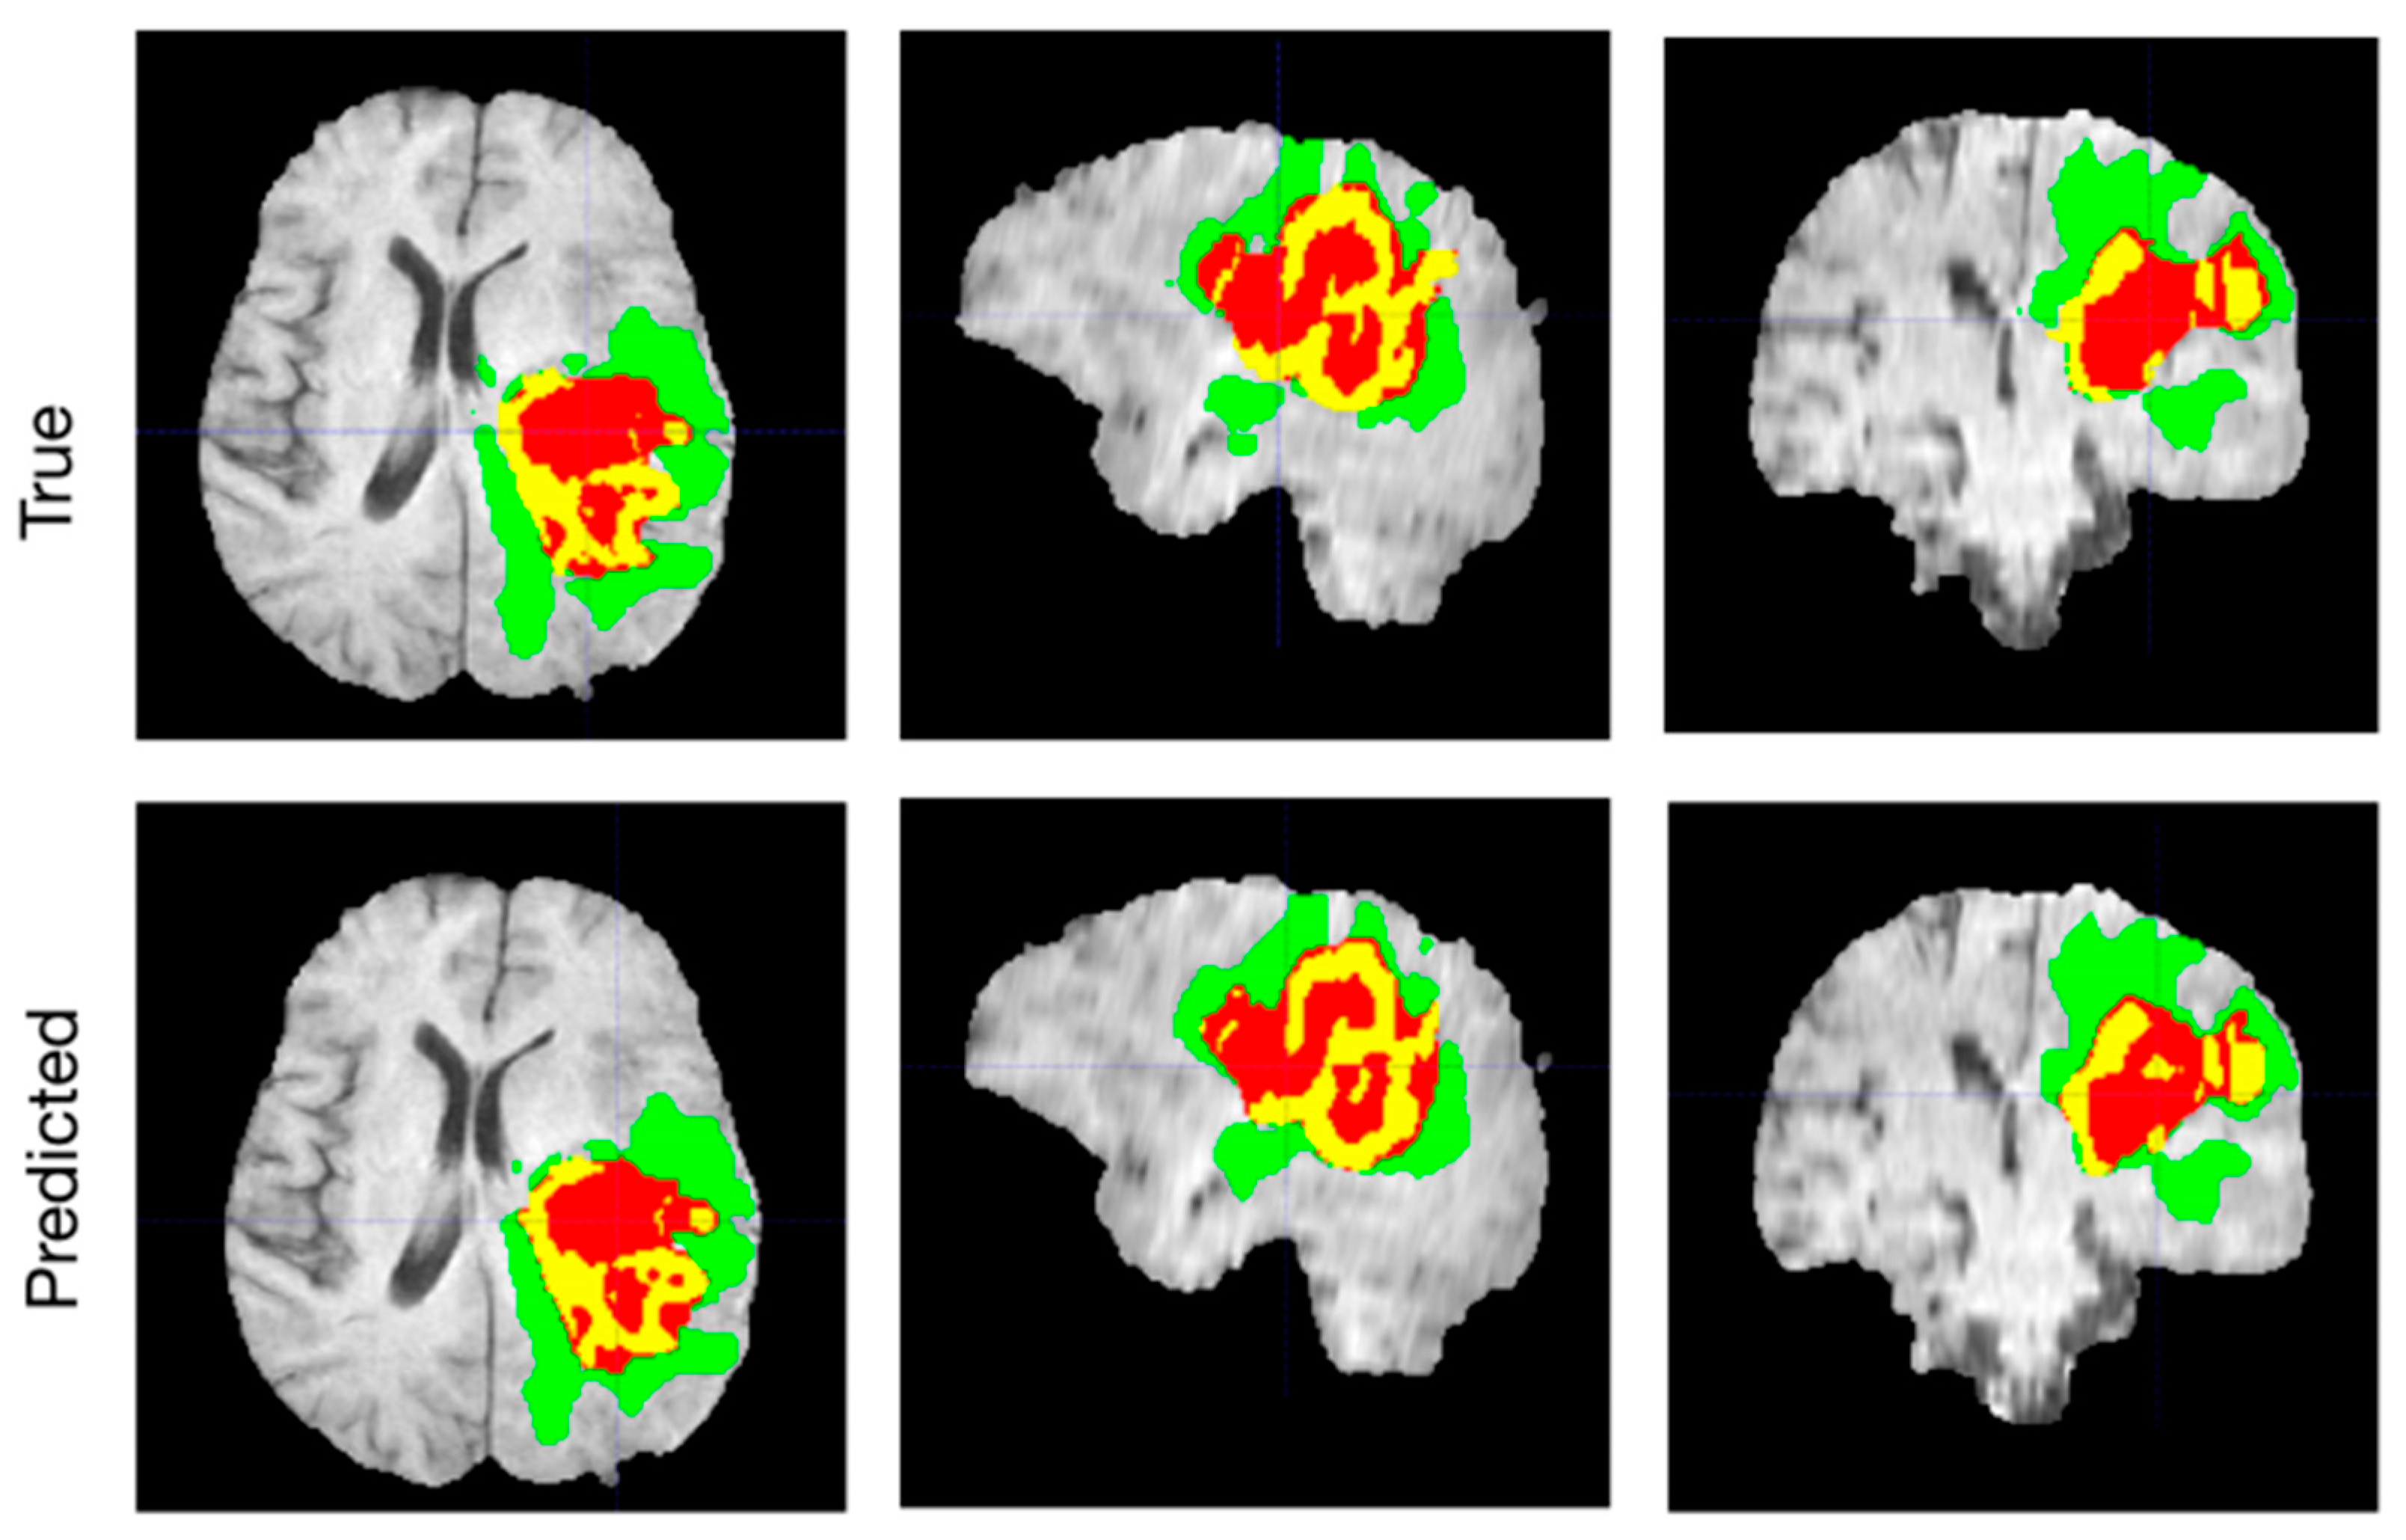

- Menze, B.; Jakab, A.; Bauer, S.; Kalpathy-Cramer, J.; Farahani, K.; Kirby, J.; Burren, Y.; Porz, N.; Slotboom, J.; Wiest, R.; et al. The multimodal brain tumor image segmentation benchmark (BRATS). IEEE Trans. Med. Imaging 2014, 34, 1993–2024. [Google Scholar] [CrossRef]

- Ghaffari, M.; Sowmya, A.; Oliver, R. Automated brain tumor segmentation using multimodal brain scans: A survey based on models submitted to the BRATS 2012–2018 challenges. IEEE Rev. Biomed. Eng. 2019, 13, 156–168. [Google Scholar] [CrossRef]